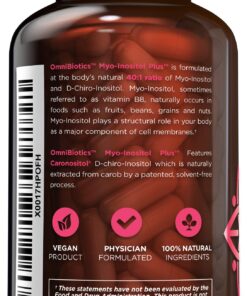

Myo-Inositol is the most abundant form of inositol which is an important

nutrient to help support the female reproductive system. D-Chiro-Inositol has

been studied for its ability to improve absorption and bioavailability.

OmniBiotics Myo-Inositol Plus with Caronositol features myo-inositol and

d-chiro-inositol at 2,000 mg and 50 mg each respectively, per serving. Myo-

Inositol Plus is a safe and effective myo inositol with d chiro supplement

option. 120 veggie caps 30 day supply These statements have not been

evaluated by the FDA. This product is not intended to diagnose, treat, cure,

or prevent any disease. Caronositol is natural D-chiro-inositol botanical

extract (minimum 95%) purified from carob pod by a solvent-free patented

process. ‣ Made In the USA within a FDA inspected, NSF and cGMP certified

facility ‣ 100% vegetarian / vegan friendly, Non-GMO ‣ Contains no gluten,

wheat, dairy soy, yeast, animal products, artificial colors, or artificial

preservatives